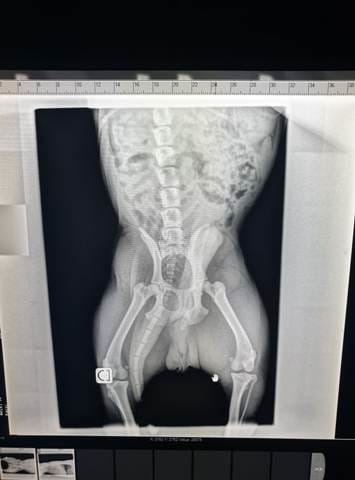

je suis allez chez le vétérinaire (j'ais payer mon loyer pour une radio mais bon quand on aime on ne compte pas :) le vétérinaire ma dit que c’était une sorte de malformation héréditaire sans être précis du tout .. et qu'il fallais attendre pour voir, du coup 5 mois plus tard ça ne fait qu'empiré , j"ai gardé les photo de la radio

Quand pensez vous ?